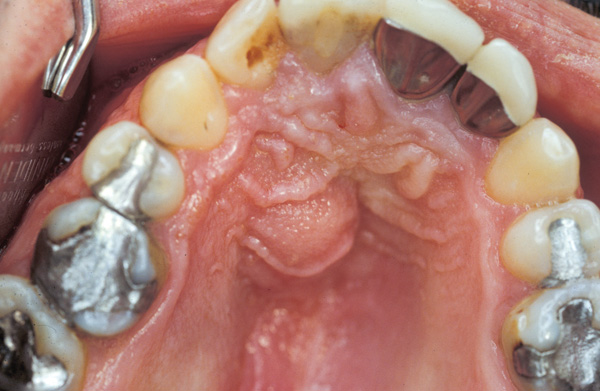

An infected area that is is fluctuant should be lanced, with anatomic factors dictating the incision line. The incision can be made with a surgical blade and must be extended to the periosteum, because there may be pus accumulated under it. A periosteal elevator is placed into the incision line and under the periosteum to seek out pus deposits. A hemostat can also be inserted into the incision and opened around 5 mm to allow pus to escape. After the incision is made, the adjacent tissue is manipulated to drive out residual pus. An antibiotic is usually prescribed for 1 week.

If pus was evacuated, the surgeon places a drain (¼-inch-thick Iodoform gauze or a Penrose drain for patients not allergic to iodine) (Figure 5 and Figure 6). An inch is cut off and ¾ of an inch is placed under the tissue. To ensure the drain does not become misplaced, a suture can be positioned through the tissue and the drain. After 3 days, if there is no pus, the drain is removed. If the site is still purulent, the drain should be removed, the wound irrigated, and a new drain placed to maintain drainage. At this juncture, it may be desirable to switch antibiotics and perform more aggressive debridement. In addition, if the patient is not responding to therapy, it would be prudent to obtain a sample for culturing and antibiotic sensitivity testing, especially if this was not done initially when the site was drained.

Figure 5 Palatal abscess due to non-vitality of tooth No. 8.

Figure 5

Figure 6 Subsequent to making an incision, a drain (iodiform gauze) is placed into the incision line to facilitate continued drainage.(Photographs courtesy of Dr. George Romanos.)

Figure 6